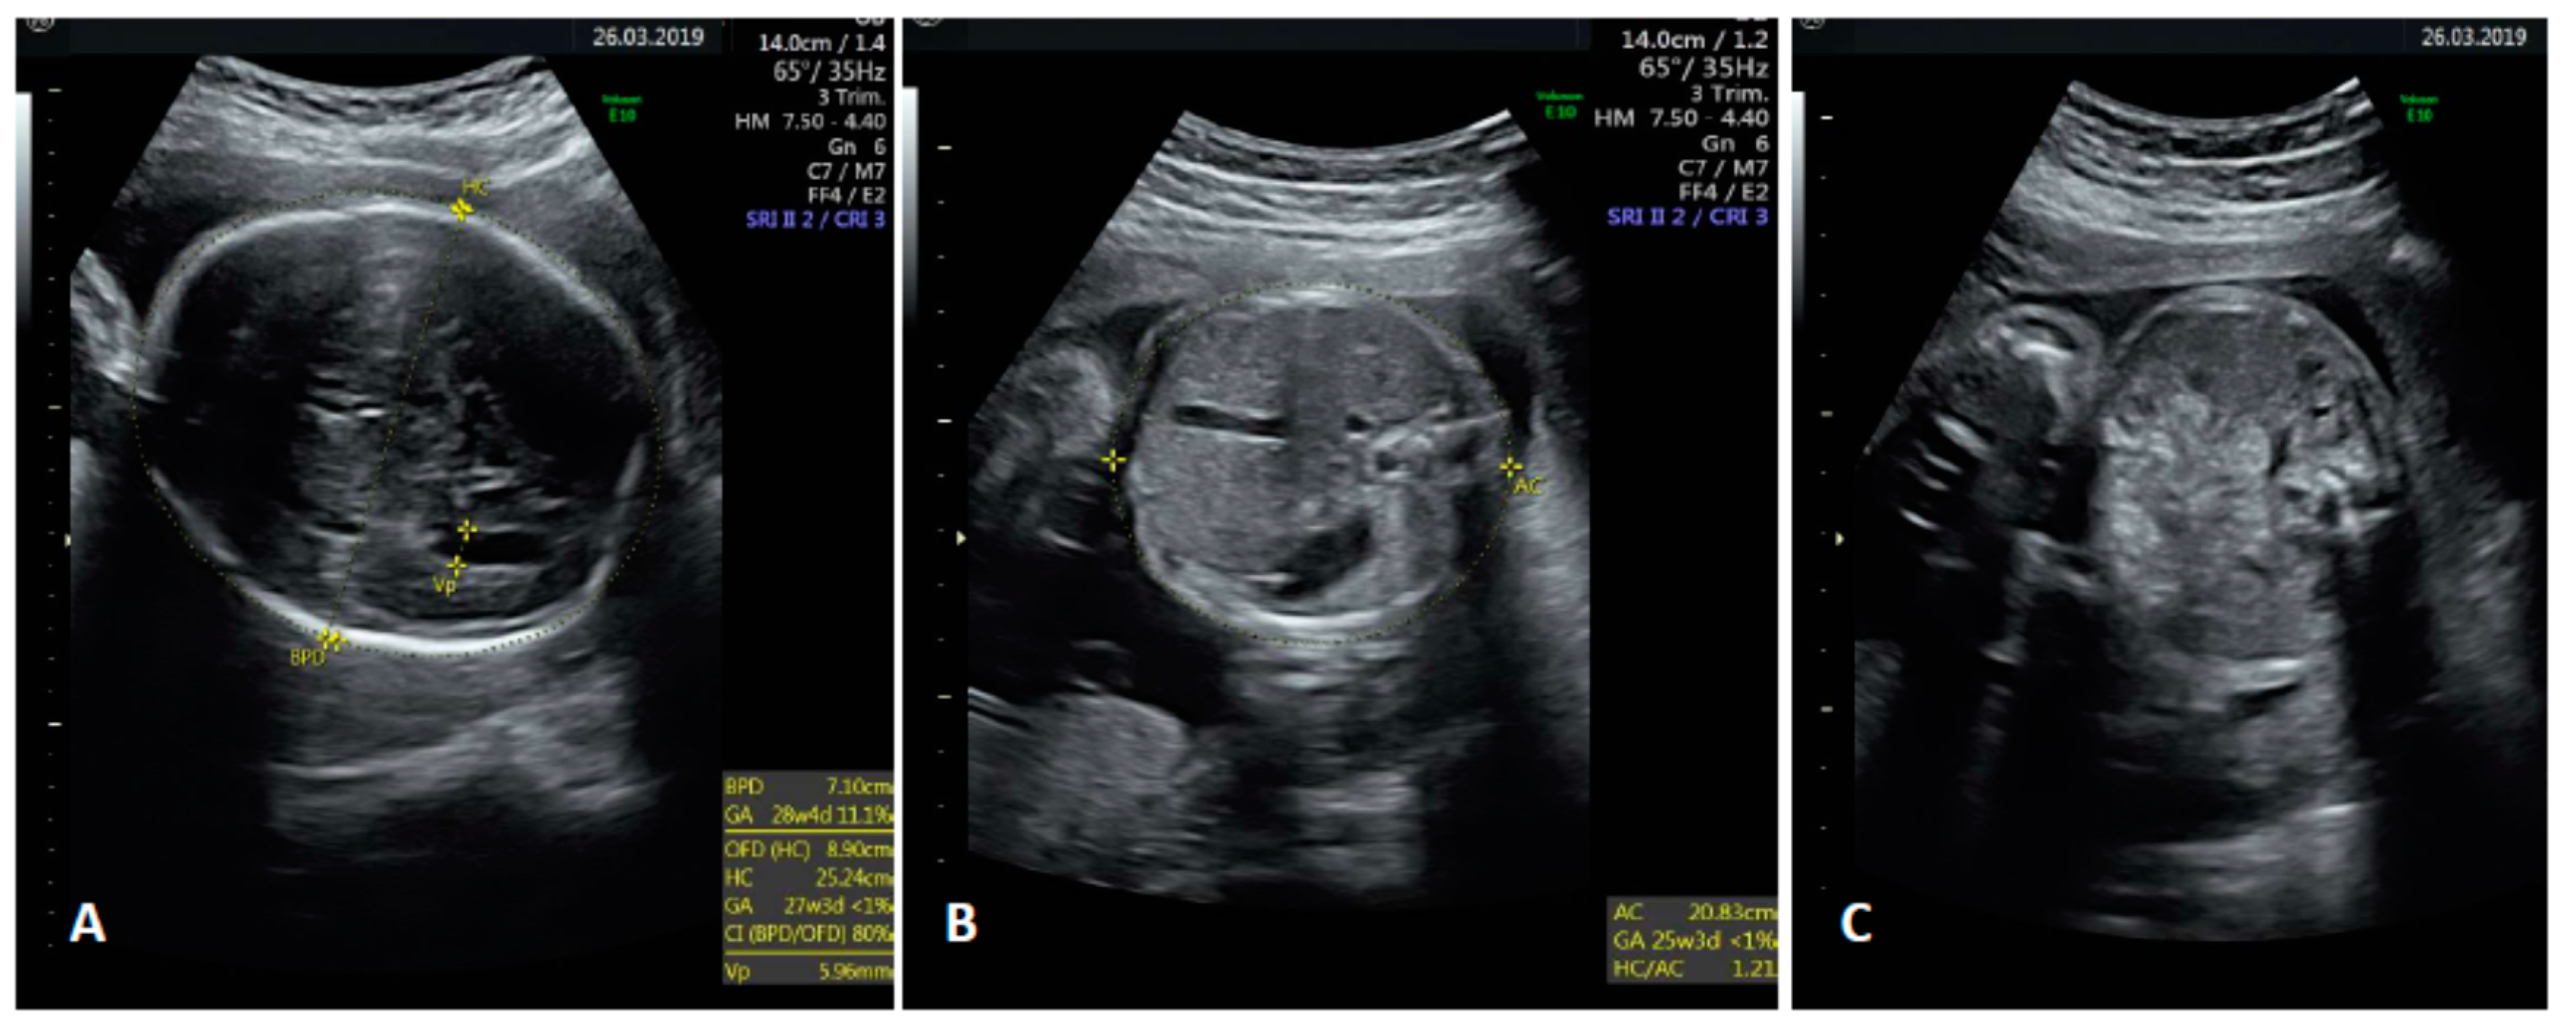

2. Case Presentation